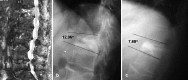

Methods: Thirty-two consecutive patients, 27 OVCFs (49 vertebral bodies [VBs]) and 5 patients suffering from VB tumor (12 VBs) were treated by balloon kyphoplasty. The mean age was 68.2 years. All patients were assessed within the first week of surgery, and then followed up after one, three and six months; all patients (27 OVCFs and 5 tumor patients) were followed up for 12 months, 17 patients (14 OVCFs and 3 tumors) were followed up for 18 months and 9 patients (8 OVCFs and 1 tumor) were followed up for 24 months (mean follow up 18 months). The correction of kyphosis and vertebral heights were measured by comparing preoperative and postoperative radiographic measurements.

Results: Thirty-one patients (96.9%) exhibited significant and immediate pain improvement: 90% responded within 24 h and 6.3% responded within 5 days. Daily activities improved by 53% on the Oswestry scale. In the OVCF group, kyphosis correction was achieved in 24/27 patients (89.6%) with a mean correction of 7.6 degrees . Anterior wall height was restored in 43/49 VBs (88%) (mean increment of 4.3 mm), and mid vertebral body height was restored in 45/49 VBs (92%) (mean increment of 4.8 mm). Edema (high intensity signal) on short tau inversion recovery (STIR) was evidenced in all OVCF patients who experienced symptoms for less than nine months and was associated with correction of deformity. Cement leakage was the only technical problem encountered; it occurred in 5/49 VBs (10.2%) of the osteoporotic group and 1/12 VBs (8.3%) of the tumor group but had no clinical consequences. The incidence of leakage to the anterior epidural space was 2%. Spinal stenosis was present in three patients (11.1%) who responded successfully to subsequent laminectomy. Retrieval of tissue samples for biopsy was successful in 10/15 cases (67%). New fractures occurred in the adjacent level in 2/27 OVCF patients (7.4%).